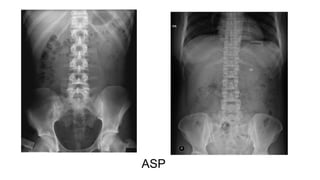

ASP

BONNE INDICATION: LA RECHERCHE

● d’une perforation

● d’une occlusion

● d’une lithiase rénale

symptomatique

● d’un CE